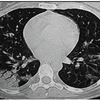

2. Interstitial lung disease 間質性肺疾患